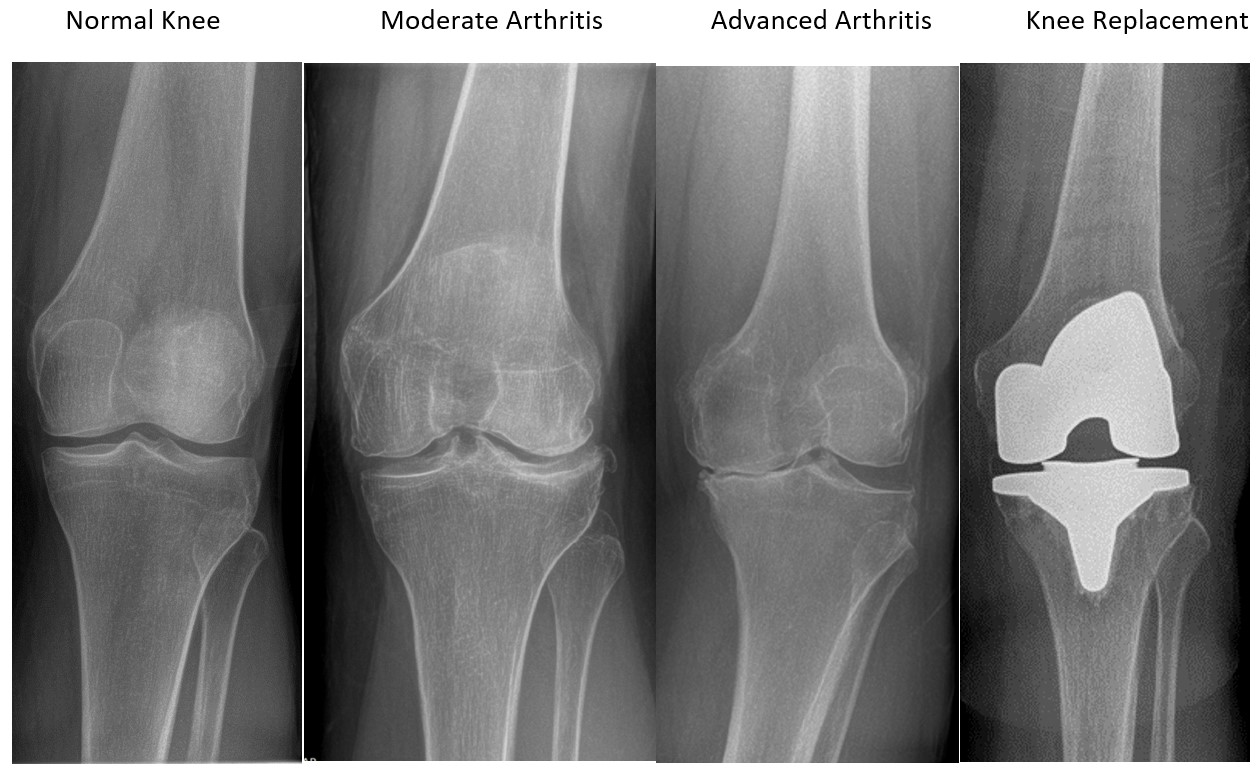

Normal knee

- Smooth contours

- Space between bones is the same

- Well aligned

Moderate Arthritis

- Bone spurs

- Slight narrowing of joint

Advance Arthritis

- Bone on bone with loss of cartilage

- Malalignment

- Large bone spurs

Knee Replacement

- Restores normal alignment of the leg

- Provides improved function and significant pain relief.